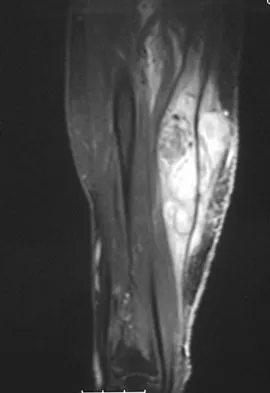

A 37-year-old woman has had intermittent paresthesias and numbness in the plantar foot for the past 6 months. She reports that the symptoms are worse with activity, and the paresthesias are beginning to awaken her at night. MRI scans are shown in Figures 6a and 6b. What is the most likely diagnosis?

Explanation

The symptoms are consistent with tarsal tunnel syndrome. Ganglion cysts are a well-known cause of tarsal tunnel syndrome. The MRI scans show a high intensity, well-circumscribed mass in the tarsal tunnel that is consistent with a fluid-filled cyst. Patients usually respond well to excision of the ganglion and resolution of the tarsal tunnel symptoms. The surrounding fat is a different signal intensity on the MRI scans, which rules out a lipoma. Synovial cell sarcoma has a heterogeneous appearance on an MRI scan. Metastatic tumors are most commonly found in the osseous structures of the foot, not the soft tissues. Rozbruch SR, Chang V, Bohne WH, et al: Ganglion cysts of the lower extremity: An analysis of 54 cases and review of the literature. Orthopedics 1998;21:141-148. Llauger J, Palmer J, Monill JM, et al: MR imaging of benign soft-tissue masses of the foot and ankle. Radiographics 1998;18:1481-1498.